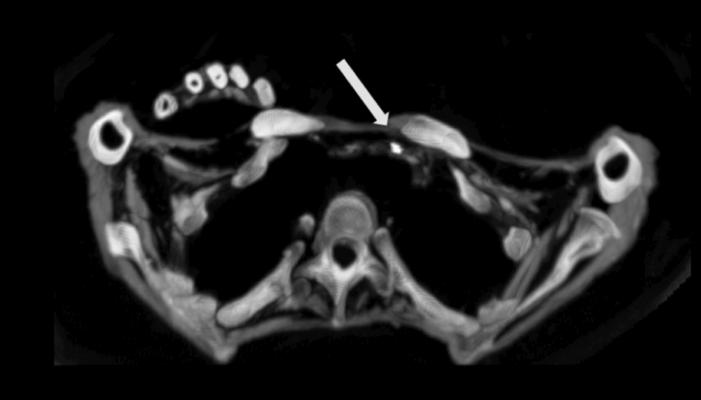

CT scan showing Egyptian mummy with calcified aortic bifurcation.

While the HORUS Study has previously reported atherosclerotic vascular calcifications on computed tomography (CT) scans in ancient Egyptians, the HORUS team’s new study was to compare patterns and demographic characteristics of this disease among Egyptians from both ancient and modern eras.[1] The scans at the Museum of Egyptian Antiquities were performed using a Siemens Somatom Emotion 16-slice CT system. The authors compared the presence and extent of vascular calcifications from whole-body CT scans performed on 178 modern Egyptians from Cairo undergoing positron emission tomography (PET)/CT for cancer staging to CT scans of 76 Egyptian mummies (3100 BC to 364 AD). Patients undergoing cancer staging were selected for the study because these scans had already been completed for this group of patients as part of their cancer care.